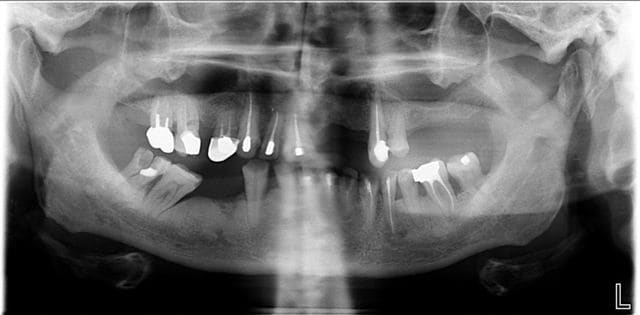

Autre cas traité de A à Z en dentisterie globale en collaboration avec un prof de ma fille, ostéopathe.

Tfm avant emp globale k5jgud - Eugenol